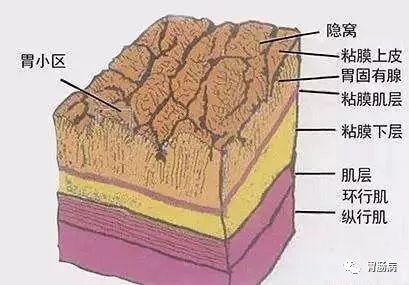

因为一般的肠型胃癌,是在胃粘膜上皮生长,胃镜进去,就一览无余,很容易发现;

而印戒细胞癌却是向胃壁外面生长,在早期,甚至在进展期,在胃粘膜表面并没有明显的改变,所以很容易漏诊。

我们的胃镜检查,就好比一个人进到屋子里观察室内的墙壁,但是壁纸下面、屋子外面的墙壁,却看不到,而这种癌就是隐藏在是墙纸下面,向外发展;

印戒细胞癌是一种组织类型,它拥有一个浪漫的名字,是根据其癌细胞在显微镜下的形态而得名,由于细胞含有大量黏液、胞质丰富、细胞核被挤压至胞质一侧,其形态呈“印戒”样,故得名。

癌细胞含有大量黏液、胞质丰富、细胞核被挤压至胞质一侧